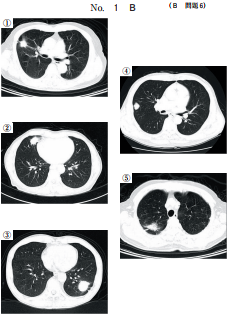

44 64 歳の男性。呼吸困難を主訴に来院した。日前に左胸痛と息切れとが出現し、 次第に増悪してきたため受診した。体温 36.2 ℃。脈拍 100/分、整。血圧 120/80 mmHg。呼吸数 20/分。SpO2 92 %room air 。眼瞼結膜と眼球結膜とに異常を認 めない。頸部リンパ節を触知しない。左胸部に呼吸音を聴取しない。血液所見赤 血球 420 万、Hb 13.0 g/dl、Ht 37 %、白血球 4,400桿状核好中球%、分葉核好 中球 60 %、好酸球%、好塩基球%、単球%、リンパ球 25 % 、血小板 21 万。 CRP 0.4 mg/dl。来院時の胸部エックス線写真別冊No. 4 を別に示す。入院後、 胸腔ドレーンを挿入したところ、直後から咳嗽と泡沫状の喀痰とが出現した。この 時点の胸部エックス線写真別冊No. 4 を別に示す。 胸腔ドレーン挿入後の病態として正しいのはどれか。